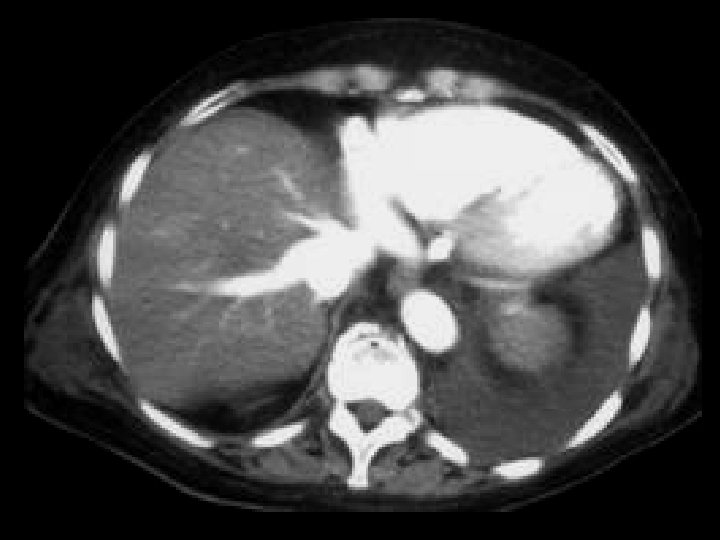

Adrenal adenoma • Findings: – Large right adrenal lesion – Isointense to liver on in -phase scan – Hypointense to liver (signal loss) on out-ofphase scan • ddx: – NONE! – This is an Aunt Minnie!